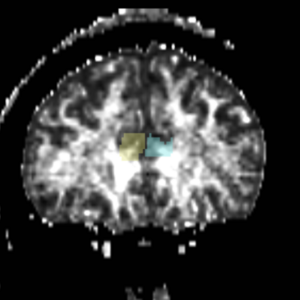

ROI 1 was drawn on the sagittal slice, 5 slices superior to the anterior commisure (Fig. 8 & 10). ROI 2 was drawn on a coronal slice where the crux of the fornix was present. It was not always the same slice for both sides (Fig. 9 & 11).

Figure 9. Coronal View of ROI 2 (left=11, right=13)

The color coding of the resulting ROIs is as follows:

ROI 1: Left & Right (7)

ROI 2: Left(8) - Right(6)